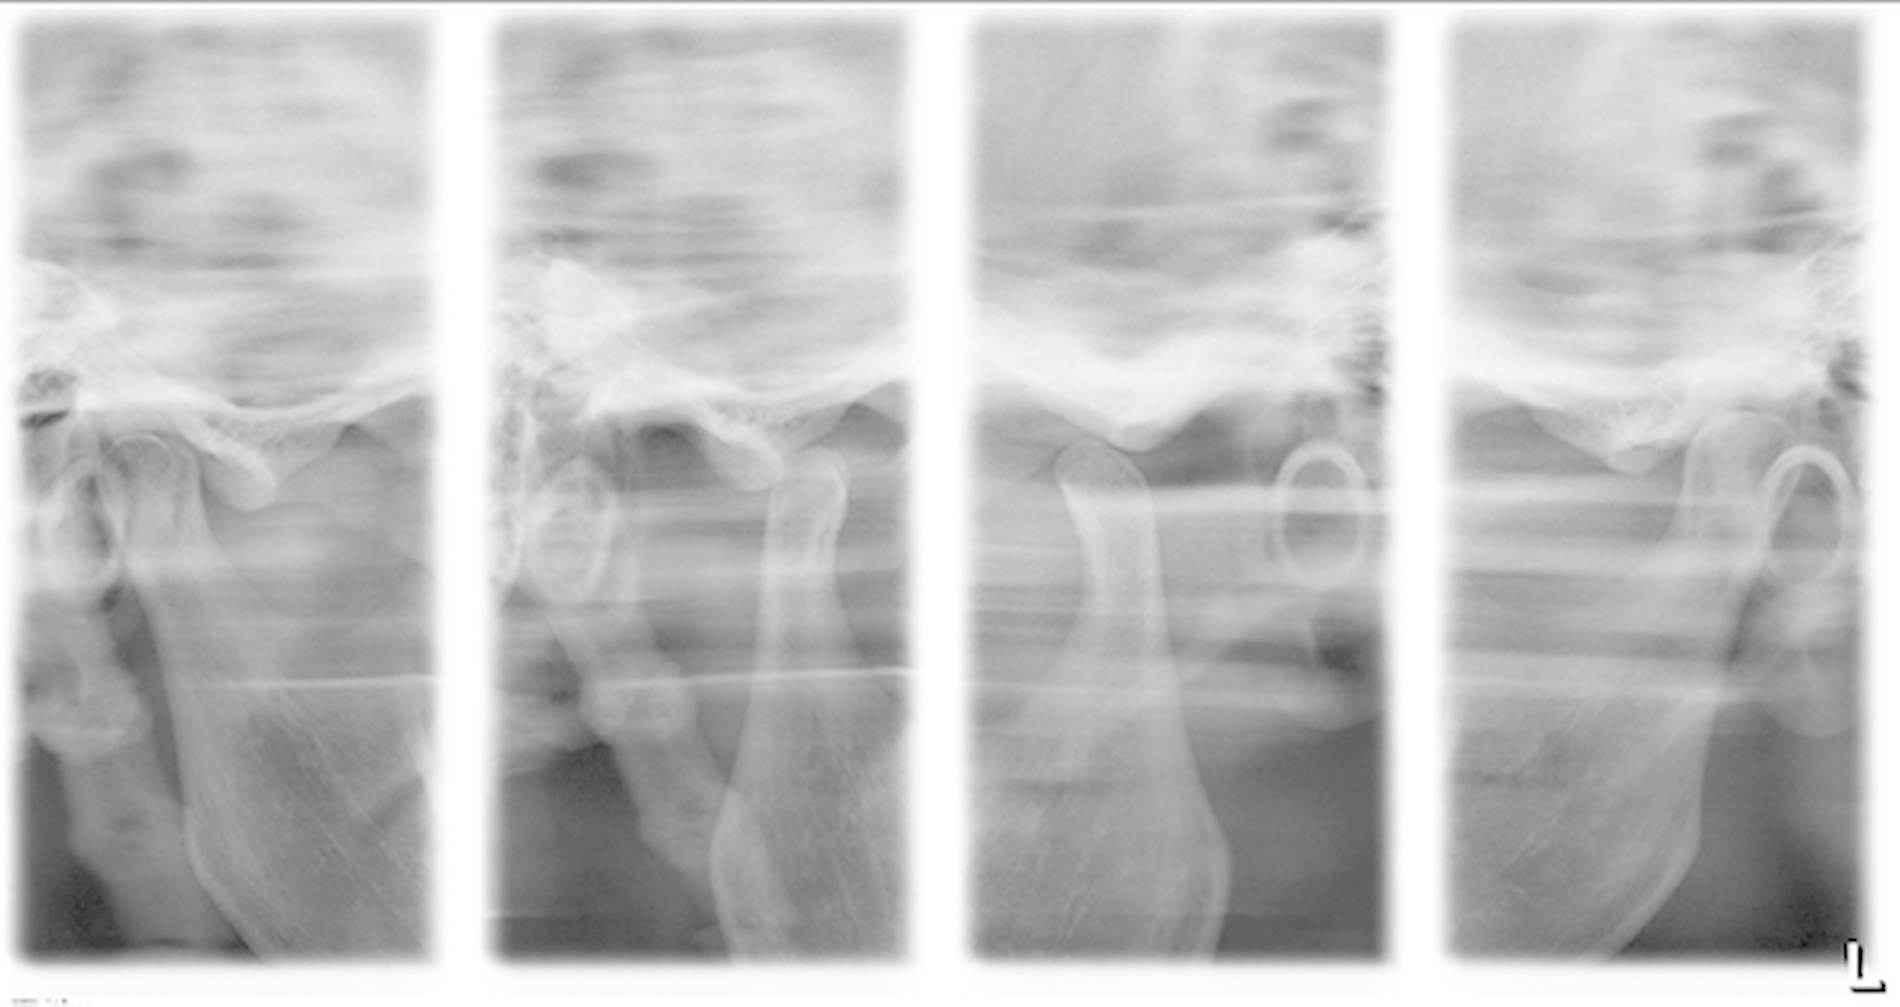

Das Orthopantomogramm zeigte einen signifikant vergrößerten Processus styloideus (47 x 11 mm) mit zusätzlich kompletter Verknöcherung des Ligamentum stylohyoideum rechtsseitig (Abbildung 1). Die Kiefergelenkfunktionsaufnahme (TM1) erbrachte den gleichen Befund (Abbildung 2).